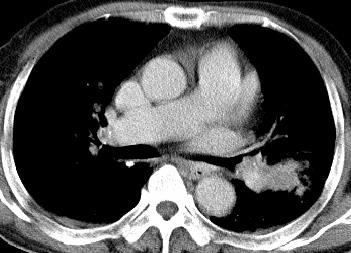

以下是引用xianxianzhongyi在2008-4-20 14:44:00的发言:[br]本人愚见:次病例短短两月的时间,呈现如此大面积实变,病变增长过于迅速,此其一。其二,病变在动脉早期既有明显强化。其三,左上叶后段及下叶背段多叶受累。其四,肺门及纵隔内未见明显肿大的淋巴结。估计层面较厚段支气管显示不清。 诊断:炎性实变可能性大。

以下是引用光影相伴在2008-4-20 14:39:00的发言:[br]支持:1)左侧中央型肺癌伴左肺上叶阻塞性肺炎。、[br] 2)双侧少量胸腔积液。